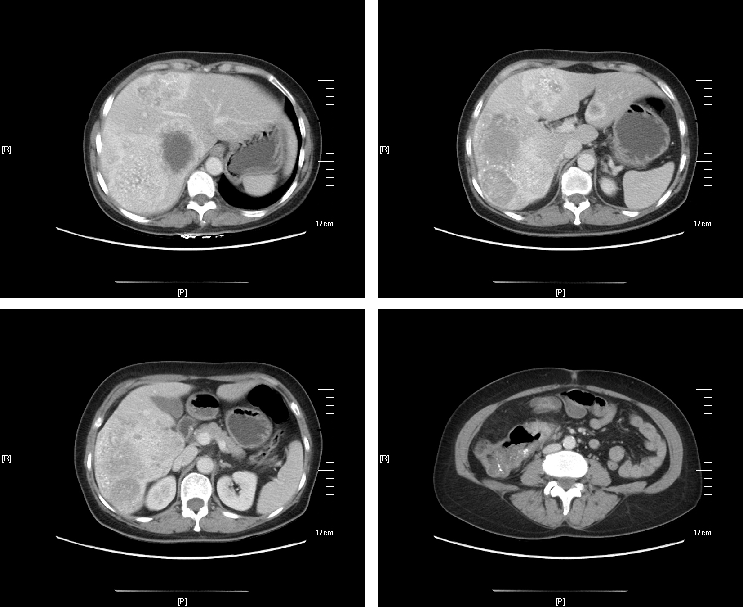

治疗后,原发灶及转移灶明显缩小,肿瘤标志物明显下降。

△治疗前

△治疗后

右肝转移灶明显缩小,左肝转移灶消失,残肝体积足够,意外达到成功转化,分期行原发灶及肝转移根治性切除手术,且原发灶和转移灶术后病理均达到pCR。术后继续完成围手术期化疗,并定期随访,现无瘤生存。